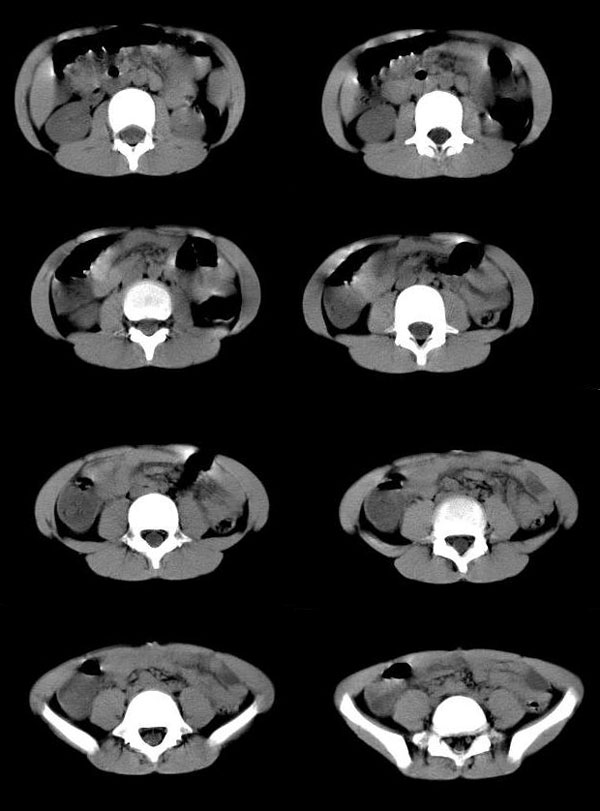

阑尾炎伴钙化,脓肿形成

男孩,9岁.2岁时在北京某大医院确诊为阑尾炎,当时保守治疗,近三天发热,下腹疼,已手术.

手术结果

阑尾炎伴钙化脓肿形成